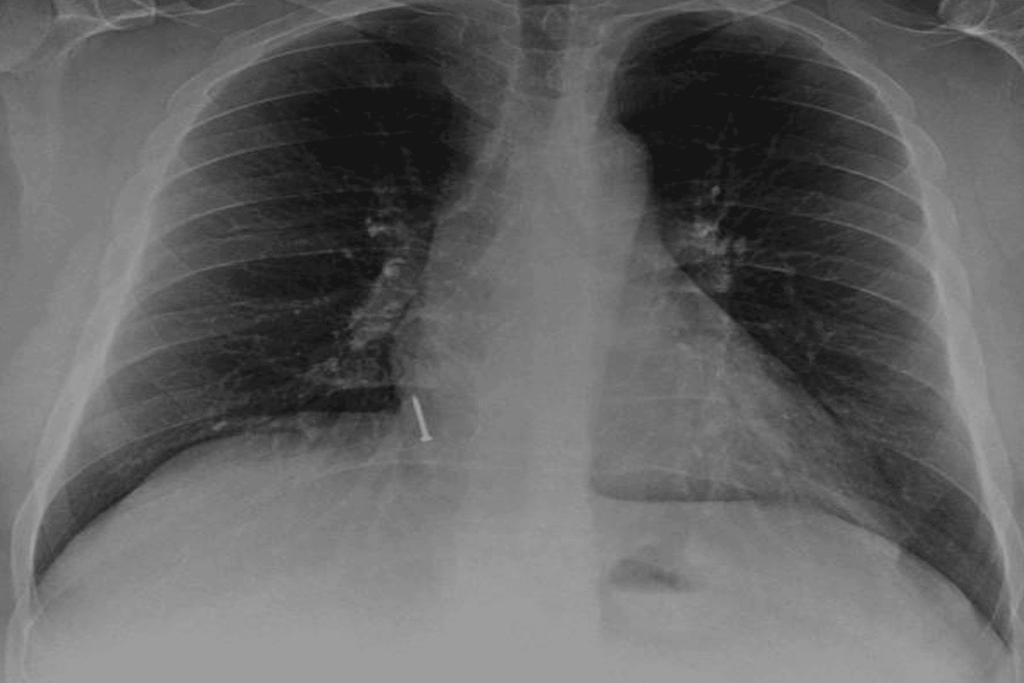

ووفقا لما قاله لصحيفة “الشعب” الصينية اليومية، فقد اضطر بعد نحو أسبوع للذهاب إلى المستشفى، وذلك بعد أن شعر بآلام مبرحة وأجريت له جراحة عاجلة لإخراج تلك المواد الحادة من داخل جهازه الهضمي، وذلك بعد أن كادت تثقب معدته وتسببت في التهابات شديدة بها.